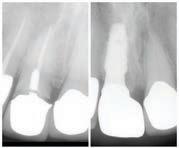

์ผ๋‹จ ๋‘ ํŒŒํŠธ๋ฅผ ๊ฐ€์ž…ํ•˜๊ธฐ ์œ„ํ•œ ๊ฐ€์ž… ์กฐ๊ฑด์ด ๋‹ค๋ฅธ๋ฐ, ์šฐ์„  ํŒŒํŠธ A๋Š” ์ผ

๋‹จ 65์„ธ๊ฐ€ ๋˜๋ฉด ๊ฐ€์ž…ํ•  ์ˆ˜ ์žˆ๋Š” ์กฐ๊ฑด์ด ๋˜์ง€๋งŒ, ๋ณธ์ธ์˜ ํƒ์Šค ๋ณด๊ณ  ์ ์ˆ˜

์— ๋”ฐ๋ผ ๋ณดํ—˜๋ฃŒ๊ฐ€ ๋‚˜๋ˆ„์–ด์ง„๋‹ค. ๋ณธ์ธ์ด ๋‚ธ, ํƒ์Šค ๋ณด๊ณ  ์ ์ˆ˜๊ฐ€ 40์  (10๋…„)

์ด์ƒ์ด๋ผ๋ฉด ํŒŒํŠธ A๋Š” ๋ฌด๋ฃŒ๋กœ ๋ฐ›์„ ์ˆ˜ ์žˆ์ง€๋งŒ, ํƒ์Šค ๋ณด๊ณ  ์ ์ˆ˜๊ฐ€ 40์ ์ด

์•ˆ ๋˜๋Š” ๊ทธ ์ดํ•˜๋ผ๋ฉด, ๋ณดํ—˜๋ฃŒ๋ฅผ ๋‚ด๊ณ  ์‹ ์ฒญํ•  ์ˆ˜ ์žˆ๋Š” ์ž๊ฒฉ์ด ์ฃผ์–ด์ง„๋‹ค.

๋งŒ์•ฝ ๋ณธ์ธ์ด ๋‚ธ ํƒ์Šค ๋ณด๊ณ  ์ ์ˆ˜๊ฐ€ 30์ ์—์„œ 39์  ์‚ฌ์ด๋ผ๋ฉด ๋งค๋‹ฌ $285

๋ฅผ ๋‚ด๊ณ  ์‹ ์ฒญํ•  ์ˆ˜ ์žˆ๊ณ , 29์  ์ดํ•˜๋ผ๋ฉด ๋งค๋‹ฌ $518์„ ๋‚ด๊ณ  ์‹ ์ฒญ ํ•  ์ˆ˜ ์žˆ๋‹ค.

ํŒŒํŠธ B๋Š” ๋ณธ์ธ์ด 65์„ธ๊ฐ€ ๋˜๊ณ , ํ•ฉ๋ฒ•์ ์ธ ์‹ ๋ถ„์œผ๋กœ 5๋…„ ์ด์ƒ ๋ฏธ๊ตญ์— ๊ฑฐ

์ฃผ ํ–ˆ์œผ๋ฉด ํŒŒํŠธ B๋ฅผ ์‹ ์ฒญํ•  ์ž๊ฒฉ์ด ๋œ๋‹ค. ํŒŒํŠธB๋Š” ๋ชจ๋“  ์‚ฌ๋žŒ๋“ค์ด ๋งค๋‹ฌ $185 (2025๋…„ ๊ธฐ์ค€)์”ฉ ๋‚ด๊ณ  ์‹ ์ฒญํ•ด์•ผ ํ•˜์ง€๋งŒ, ๋ณธ์ธ์˜ ์ธ์ปด์ด ๋งŽ๋‹ค๋ฉด, ๋งค

๋‹ฌ ์ถ”๊ฐ€๋กœ ๋ถ€๊ณผ๋˜๋Š” ๊ธˆ์•ก์ด ์ปค์ง„๋‹ค.

๊ทธ๋ฆฌ๊ณ  ์ด ์ธ์ปด ๊ธฐ์ค€์€ ๋ณธ์ธ์˜ 2๋…„ ์ „ ํƒ์Šค๋ณด๊ณ ์„œ๋ฅผ ๊ธฐ์ค€์œผ๋กœ ํ•˜๊ธฐ ๋•Œ

๋ฌธ์— ํ˜„์žฌ๋Š” ๋ณธ์ธ ์ธ์ปด์ด ์—†์–ด๋„ ๋งŒ์•ฝ 2๋…„ ์ „์— ์ง‘์„ ํŒ”๊ฑฐ๋‚˜ ํ•ด์„œ ํƒ์Šค

๋ณด๊ณ ๋ฅผ ๋งŽ์ด ํ–ˆ๋‹ค๋ฉด, ๊ทธ์— ๋”ฐ๋ผ ๋ณดํ—˜๋ฃŒ๋ฅผ ๋” ๋‚ด์•ผ ํ•œ๋‹ค. (*๋„ํ‘œ์ฐธ์กฐ)